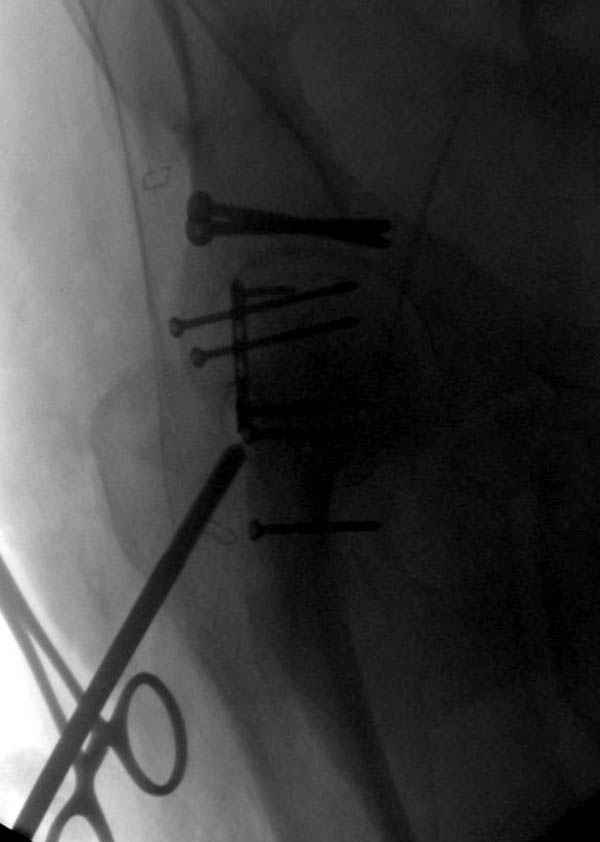

Наш недавний случай перкутанной фиксации "методом

Сиэтла" спицами 2.8 мм с резьбой на конце.

Наличие рентген контроля (ЭОП) помогает во время

репозиции и фиксации, но многие коллеги умудряются без рентгена фиксировать несколькими спицами перкутанно.

Из-за тенденции миграции осторожно со спицами,

особенно у пожилых, слабые кости не выдерживают

нагрузку, были случаи миграции, обнаруженные при первом же амбулаторном приеме, поэтому методика Лазарева напряженными спицами более приемлема, особенно у тех, кто испытывает нехватку фиксирующих конструкций (на сайте

имеется описание техники).

Головка плечав небольшом варусе или это проекционное?

-Головка плеча в небольшом варусе или это

проекционное?

Да, там имеем небольшой варус, надеемся, что в будущем проблемы не будет.

Из-за большого обьема конечности доступ к бугорку был затруднен, предварительно зафиксированный шуруп не удержал бугорок, поэтому фиксацию провели толстыми нитками. Состоятельность фиксации бугорка обычно проверяем во время операции, под рентген контролем проводится движения конечности, особенно приведение.